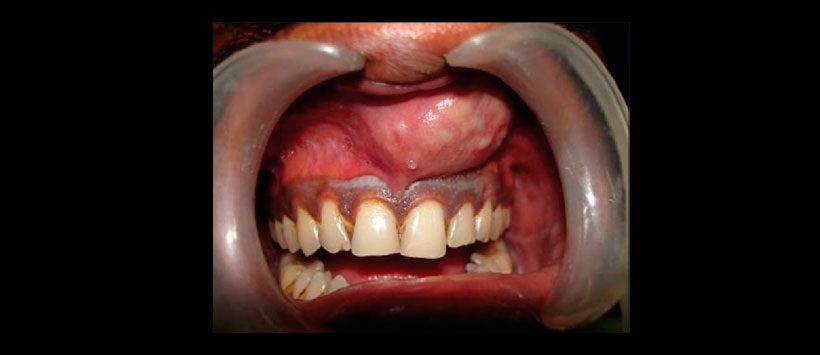

Figura 2: Fotografía intraoral que muestra un aumento de volumen a nivel de la tabla ósea vestibular con borramiento del fondo de surco que se extiende de la zona de pieza 11 a la zona de la pieza 24.